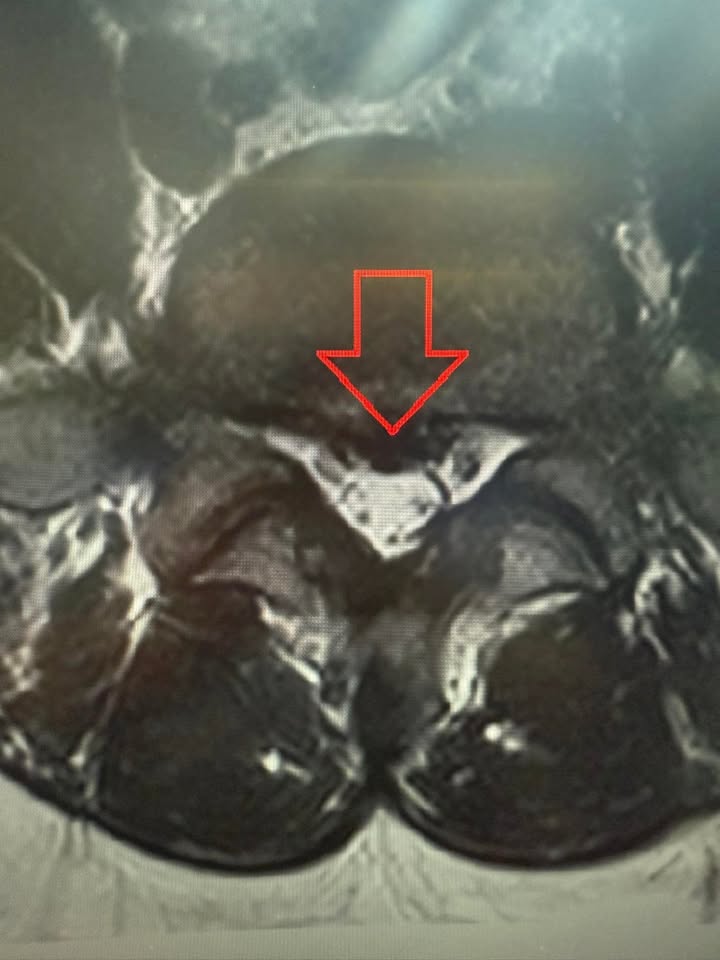

我建議他做一次核磁共振(MRI),來看看真正的問題出在哪裡。當影像出來的那一刻,我心裡有了答案——這不是肌肉的問題,而是椎間盤突出!

那畫面上清清楚楚顯示,L5-S1的椎間盤向後突出,壓迫著神經,這才是折磨他的罪魁禍首。難怪過去那些針灸、電療,甚至疼痛治療都無法讓他真正痊癒,因為沒有解決問題的根源。